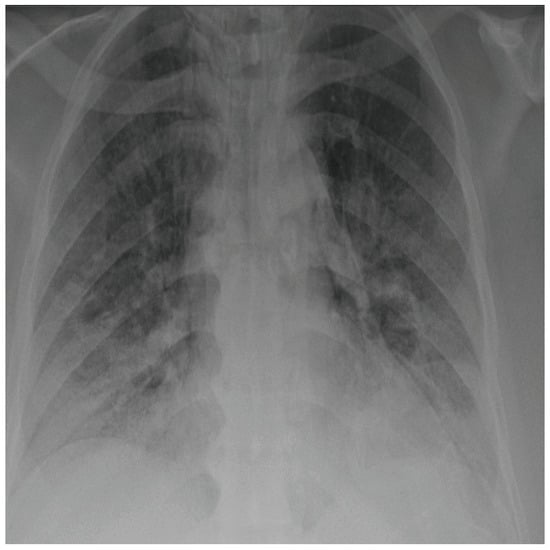

COVID-19 patients who have clinical symptoms are more likely to show abnormal CXR [9]. The main findings of recent studies suggest that these lung images display patchy or diffuse reticular–nodular opacities and consolidation, with basal, peripheral, and bilateral predominance [10]. For example, Figure 1 shows the CXR of a mild case of lung tissue involvement with right infrahilar reticular–nodular opacity. Moreover, Figure 2 shows the CXR of a moderate to severe case of lung tissue involvement. This CXR shows right lower zone lung consolidation and diffuse bilateral airspace reticular–nodular opacities, which are more prominent on peripheral parts of lower zones. Similarly, Figure 3 shows the CXR of a severe case of lung tissue involvement. This is caused by diffuse bilateral airspace reticular–nodular opacities that are more prominent on peripheral parts of the lower zones, and ground glass opacity in both lungs predominant in mid-zones and lower zones. On the other hand, Figure 4 shows an unremarkable CXR with clear lungs and acute costophrenic angles (i.e., normal).

Figure 4.

Normal CXR.